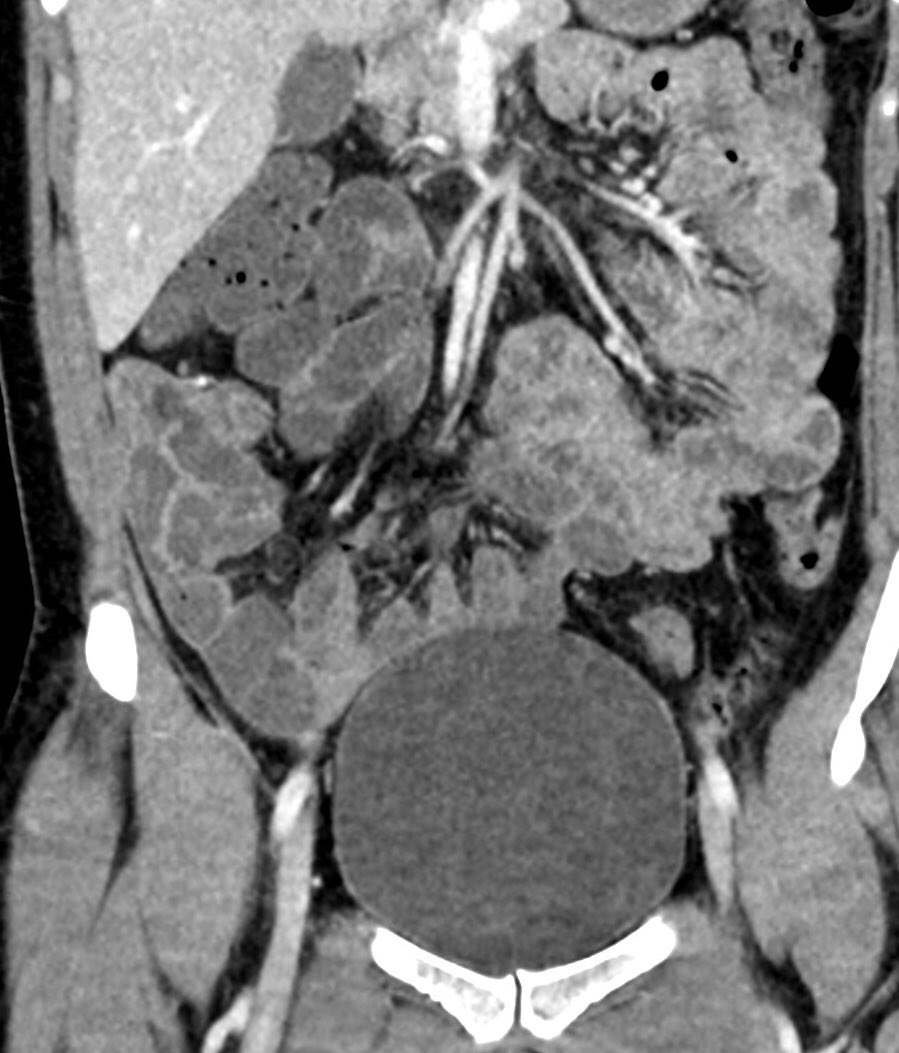

The mass in this 30ish year old female in the ER post trauma is?

#RadRes#MedTwitter#FOAMed#FOAMradpic.twitter.com/3miaLNbQj6 -